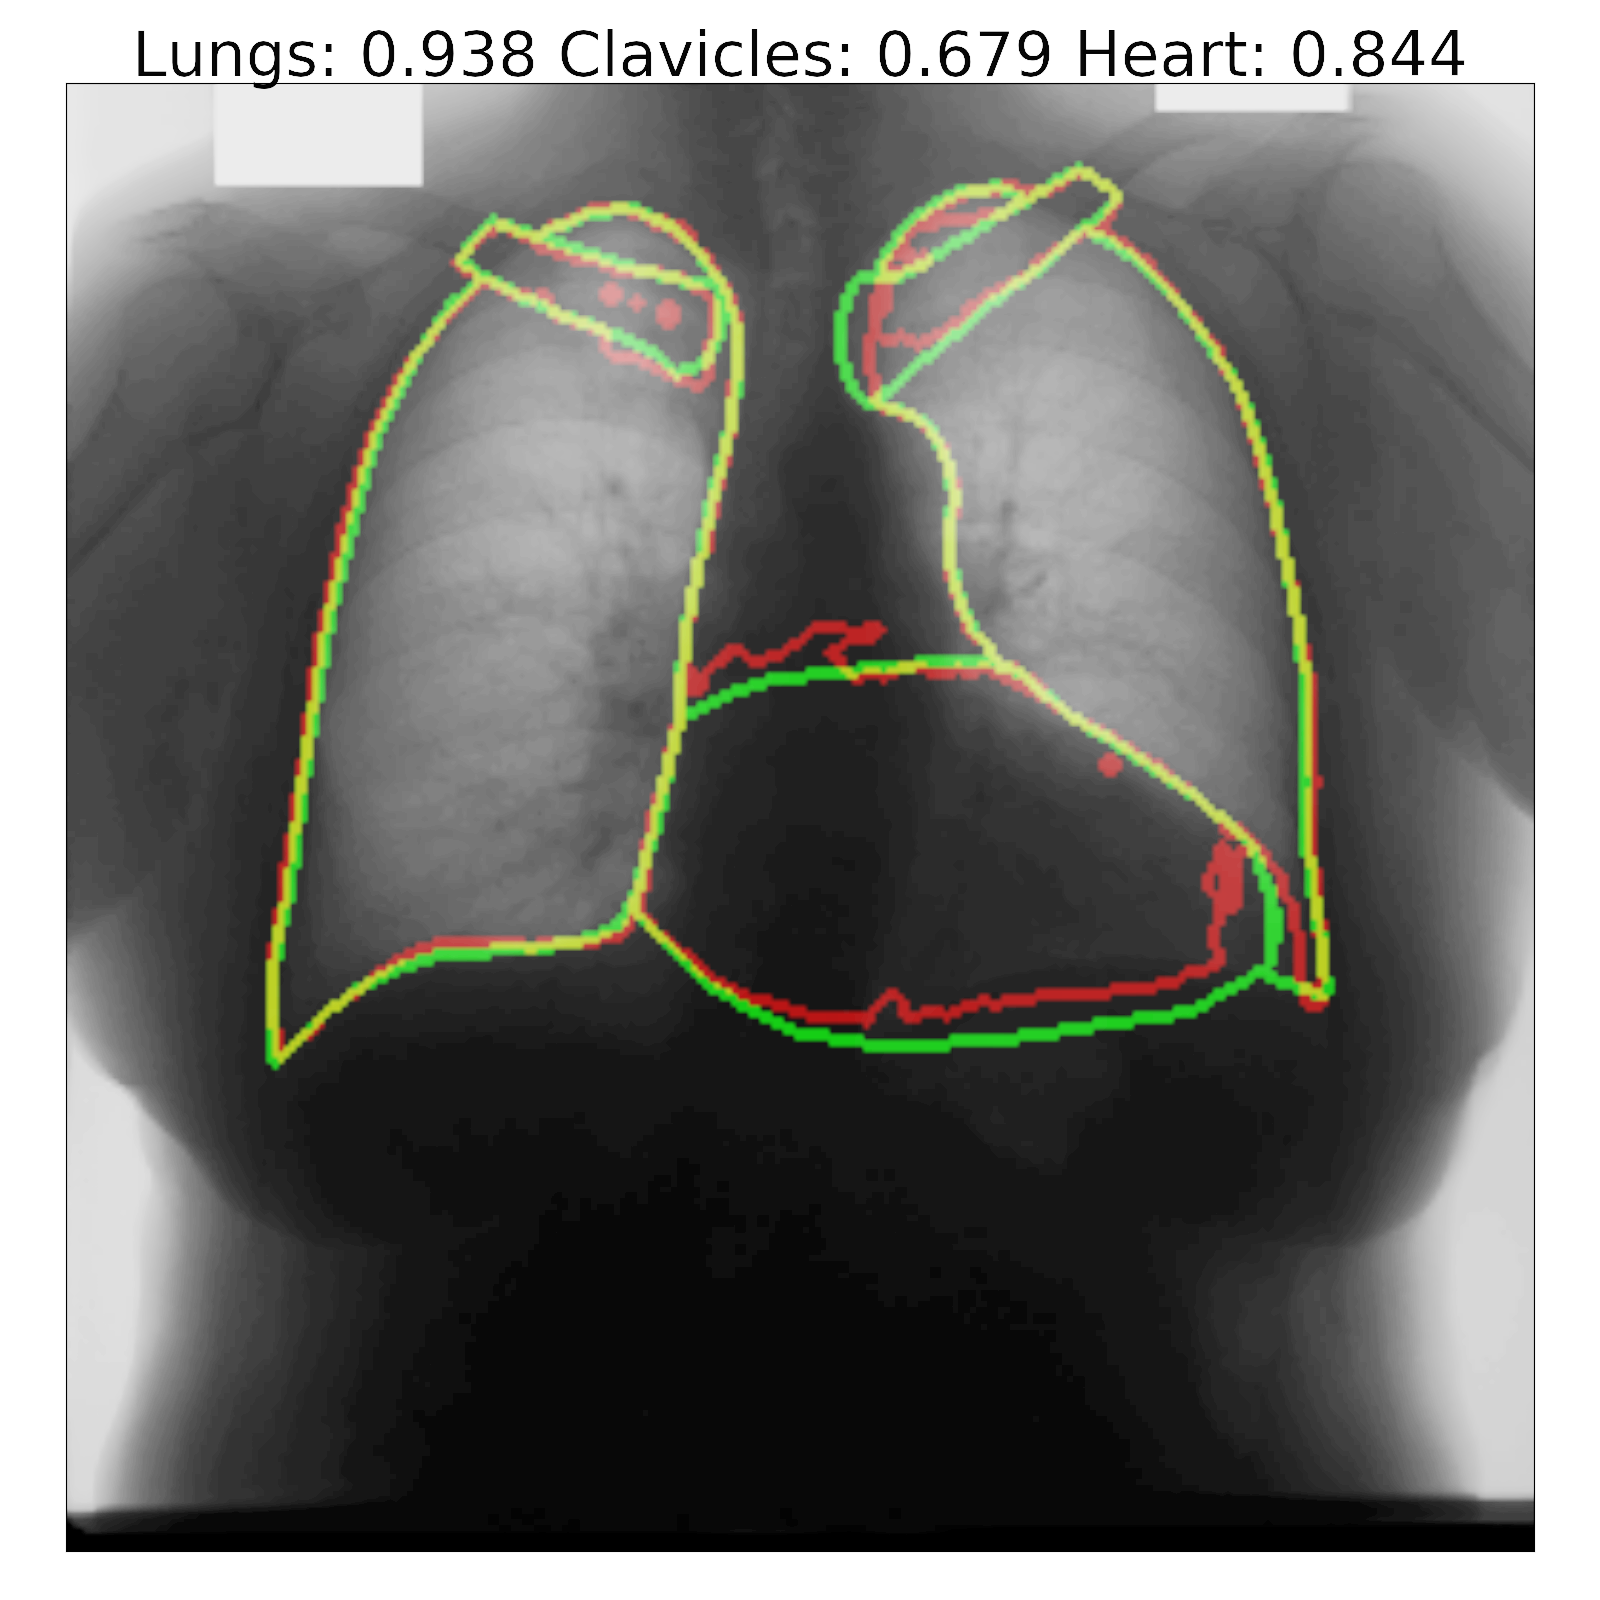

Figure 7: Segmentation results and corresponding Jaccard scores on some images for U-Net (top row) and proposed InvertedNet with ELUs (bottom row). The contour of the ground-truth is shown in green, segmentation result of the algorithm in red and overlap of two contours in yellow.

Fig. 7 shows a few examples of the algorithm results for both successful and failed cases for U-Net (top) and the InvertedNet  trained with the ELU and loss function based on the Dice coefficient. The white boxes show Jaccard scores for lungs, clavicles and heart. To extract the shape contours of the segmentation and ground-truth, we used a morphological outline extraction algorithm on both segmentation result and reference masks. The contour of the ground-truth is shown in green, the segmentation result of the algorithm in red and the overlap of two contours in yellow colors.